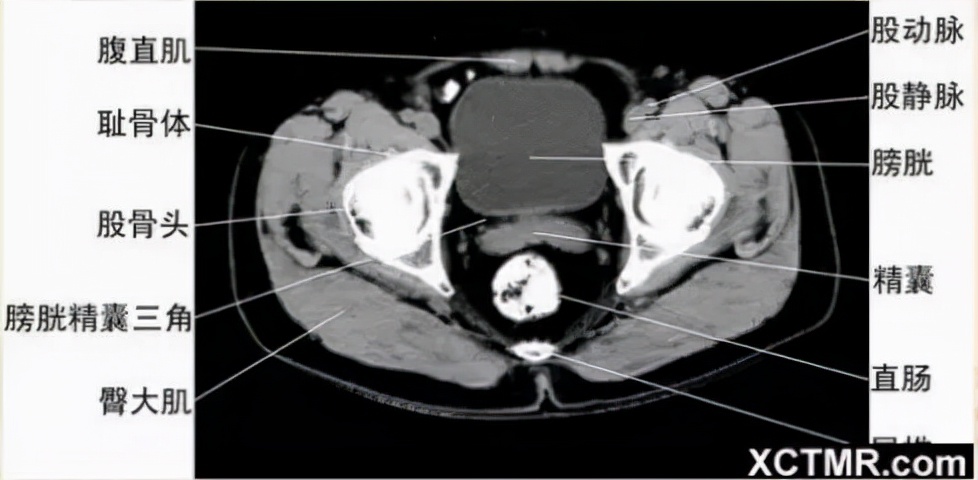

男性盆腔CT断层